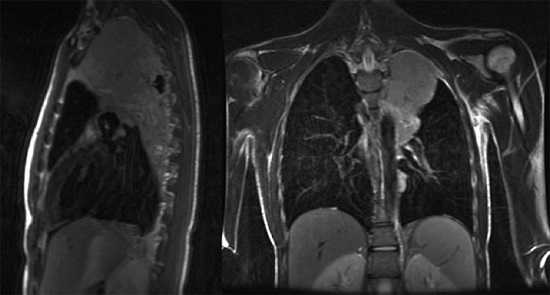

- Магнитно-резонансная томография или компьютерная томография опухоли. Эти исследования позволяют адекватно оценить распространенность опухолевого процесса, прилежание опухоли к магистральным сосудисто-нервным структурам, степень вовлечения прилежащих анатомических структур и как следствие сделать вывод о возможности проведения хирургического лечения.

Диагноз выставляют на основании осмотра, данных инструментальных исследований и результатов биопсии. Пациентов с десмоидной опухолью направляют на УЗИ, КТ и МРТ. Наиболее информативным методом исследования, позволяющим установить границы опухоли и степень ее инвазии в окружающие ткани, является магнитно-резонансная томография. При необходимости назначают ангиографию сосудов и другие исследования. При прорастании сосудов, нервов, внутренних органов и костных структур может потребоваться консультация сосудистого хирурга, невролога, абдоминального хирурга, торакального хирурга, травматолога, ортопеда и других специалистов.

Что показывает МРТ органов грудной клетки

В грудной клетке расположено множество жизненно важных органов, патологии которых сложно диагностировать классическими способами: они скрыты за костями грудины, ребрами, позвоночником, мягкими тканями. Информативным способом, который способен показать структуру, а также функциональность органов, расположенных здесь, врачи называют МРТ — магнитно-резонансную томографию с контрастом или без него. Метод идеально подходит для исследования находящихся внутри грудины органов, сосудов, желез, лимфоузлов, но наиболее эффективным его считают в диагностике опухолевых процессов.